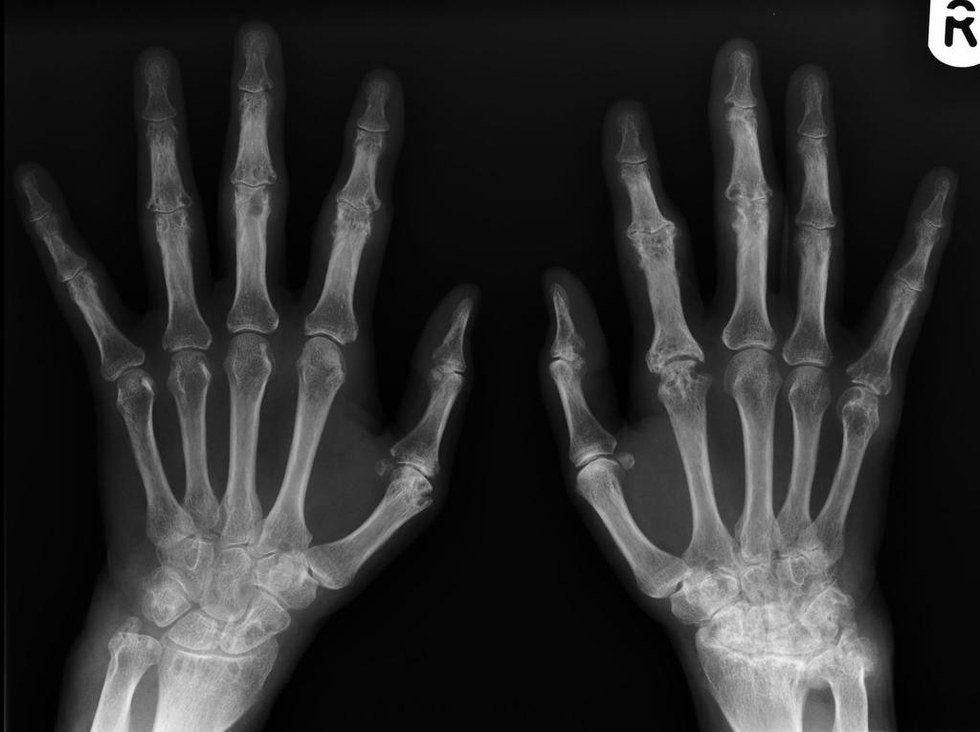

Pain. One of the elements of life that can make you crumble or make you resilient enough to eradicate every ounce of pain that may circulate in your veins. Pain can be mental or physical, however, the chronic illness that I possess makes me suffer in both ways. Rheumatoid arthritis is when “the body’s immune system attacks its own tissue, including joints; it affects joint linings, causing painful swelling over long periods of time, the inflammation associated with rheumatoid arthritis can cause bone erosion and joint deformity.” Living with this particular illness has forced me to be brave, and the illness acts as an reminder for me to know that there’s some things in life that we can not control.

As a couple weeks passed by, my weight decreased drastically due to not consuming the nutrients that I needed to function properly. I couldn’t eat because of the medication was making me feel sick. I loathed looking at myself or going in the shower. I was so malnourished and disgusting. Every time I observed myself in the mirror, I always saw a skeleton in my view. I cried myself to sleep each night. I just couldn’t take it anymore. Especially when my father and I go into huge arguments about my weight loss and loss of appetite. He began to believe that I was just being stubborn and having this desire or temptation to lose weight. Every day, my father and I fought. I was drowning in my own tears. I wanted to escape, but didn’t know how. I was in so much pain physically, emotionally, and mentally. As the days continued to pass by, my body continued to ache, lose weight and became extremely drained and malnourished. So my family and I decided that it would be best to go to the hospital, get my appetite back, and my mental stability back into place. I had a huge desire to discover the other half of me, even though I could not see it visually. I felt a positive aura lingering within my austere and hollow atmosphere, but I did not believe that I had possessed the strength to reach out towards ambition and positivity. And I felt that I had no desire to obtain ambition and positivity. When I was hospitalized, I was so fearful. I felt so alone and useless. I wanted to disappear and disguise with the wind currents. I could not deal with the physical and psychological pain. I was so tired with burdening my friends and family with all of my personal predicaments. They deserved so much more than observing me in pain and destructing my own mind with negative coping skills and mindsets. I did not care about the pain and emptiness making me whole with its ounces of despair and venom. I wanted those particular elements to conquer me in order to cease my pain. My existence. It was digging the deeper layers of myself; layers that I was extremely scared to acknowledge. Each day at the hospital, I was making some progress with recovery. Some days were tough than others, but I was still trying, no matter how much pain I was in. Then, one day, my doctor revealed that I was diagnosed with a major depressive disorder, anxiety and rheumatoid arthritis. I instantly was in tears when he announced that I had rheumatoid arthritis. I did not want to believe him, and I strongly felt that it was impossible for me to have arthritis at such a young age. It felt like the negativity just kept winning and conquering me every step of my journey. I just wanted all of this end. I just wanted to be happy with myself and life. I just wanted the pain to stop.

Living with rheumatoid arthritis has forced me to be resilient, and the illness acts as an reminder for me to know that there’s some things in life that we can not control. Even though I struggle with accepting and dealing with experiencing chronic pain every day, it has made me so much stronger. It made me realize that I conquer any struggle in my path in the present and future. It really showcases my passion and bravery to continue to live life happily, and to continue to diffuse my story in order to linger positivity, strength, and understanding towards others that suffer with chronic illnesses as well. Also, it displays my strength that I possess in order to prevent myself from living in fear. Now I adore the silence. I adore feeling alive. Especially when it's 2 a.m. and I’m sitting in my dark room. Playing all the songs I love the most. And the world seems so quiet. So calm, collected, and clear as water flowing in streams.My mind feels so light; the emptiness isn’t weighing me down on the pavement. I’m not sinking down with the growing roots. My heart isn’t crushed. I feel more connected with the world. Even though we’re distant, I still feel like our souls coexist. I feel like all of the people of my past and present are close to my heart.Timeline of events consuming me.Leaving me empty, but yet whole. Once you’re complete, you indulge so much passion, insight, and strength, that you reveal an incredible change that sets your free from all of the pain and suffering.